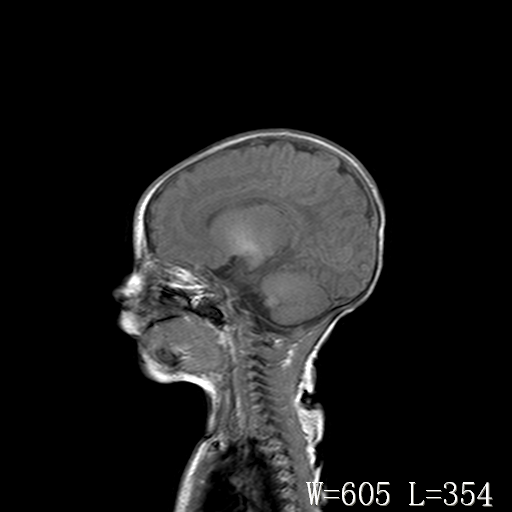

男,4天,发复抽搐1天。

脑干形态欠规则,信号增高,不知怎么解释?

脑干背侧面t1高信号是,新生儿正常已经髓鞘化好的部位